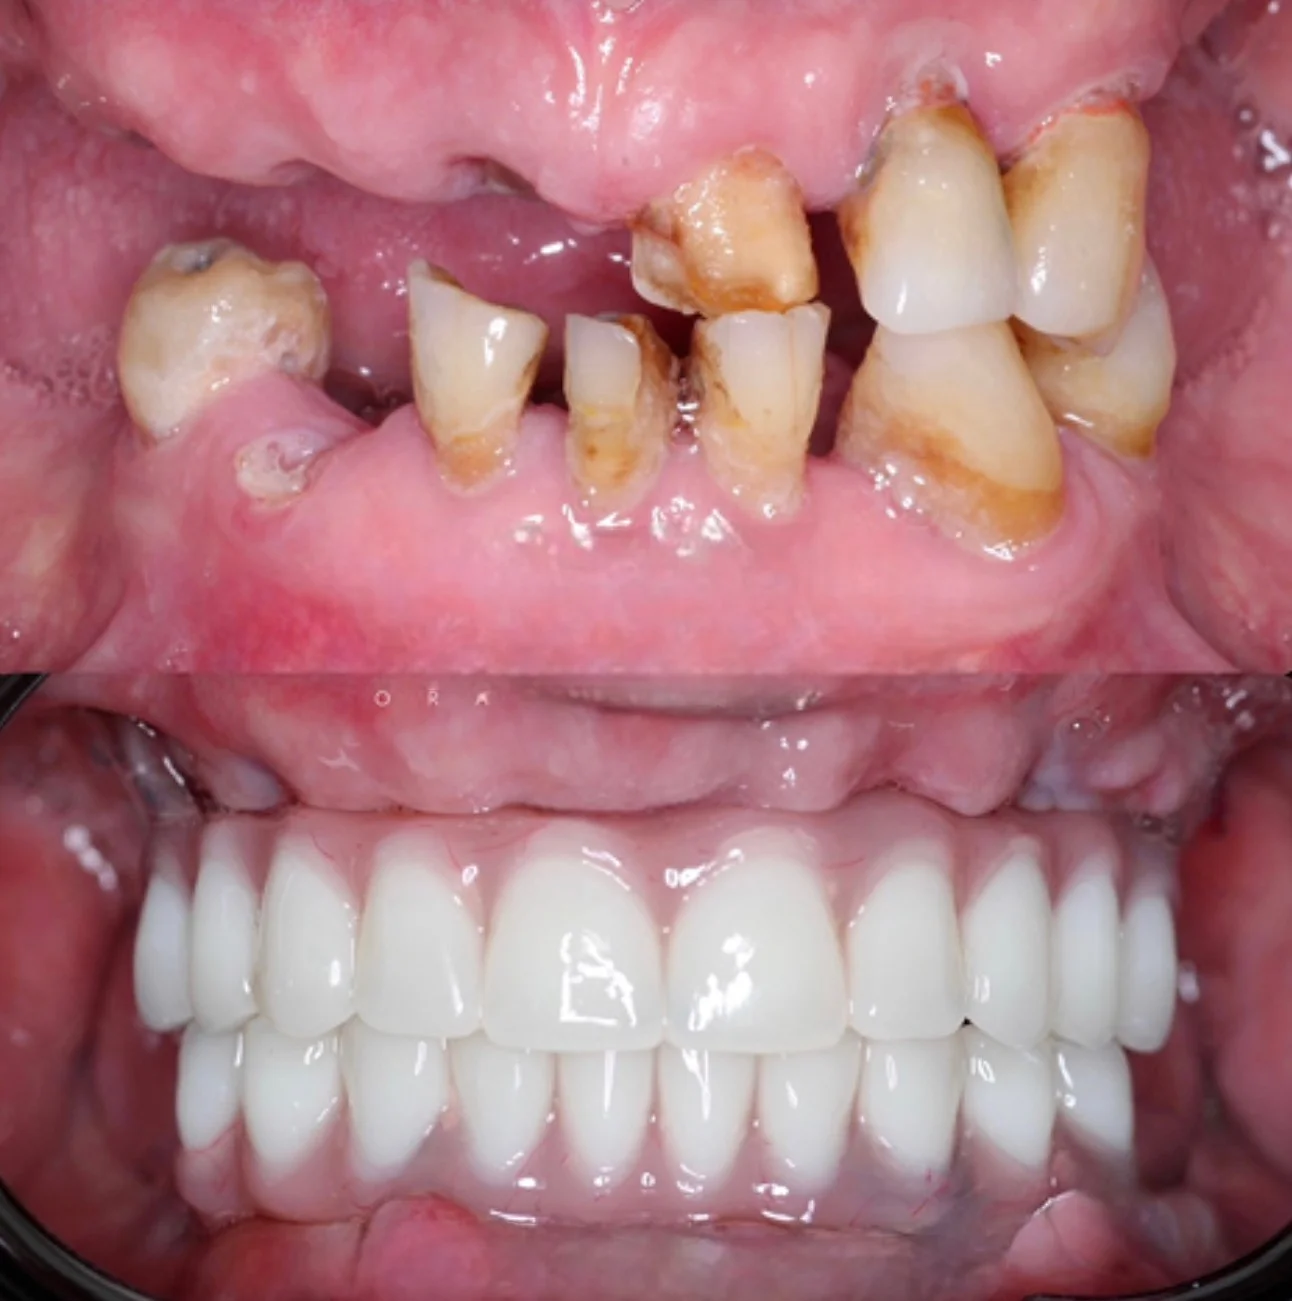

Долгое время пациентка стеснялась улыбаться и избегала фотографий из-за проблем с зубами и неудобных съёмных конструкций. Она откладывала лечение, считая, что восстановление будет долгим и тяжёлым. Отсутствие зубов на верхней и нижней челюсти требовало надёжного и долгосрочного решения.

На консультации мы подробно обсудили все варианты и выбрали современное и комфортное решение. Было выполнено полное восстановление зубных рядов по концепции All-on-6 с немедленной нагрузкой. В день операции установлены имплантаты и несъёмные протезы.

Сегодня пациентка улыбается уверенно, свободно общается и возвращается к привычной активной жизни без прежних ограничений.